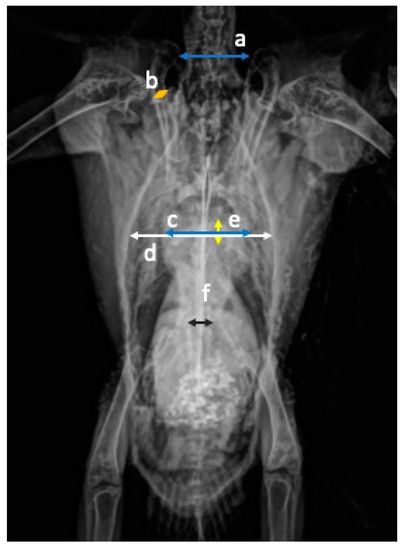

Radiographic Measurements of the Cardiac Silhouette and Comparison with Other Radiographic Landmarks in Wild Galahs (Eolophus roseicapilla)

by Petra Schnitzer, Shivananden Sawmy and Lorenzo Crosta

Animals 2021, 11(3), 587; https://doi.org/10.3390/ani11030587 - 24 Feb 2021

Background: Part of the diagnostic workup for cardiac diseases is radiographic imaging. To determine an enlarged heart, species-specific reference values are necessary. Wild birds are rarely diagnosed with cardiac disease, and only a few studies have been done to investigate the cardiac silhouette [...] Read more.

Background: Part of the diagnostic workup for cardiac diseases is radiographic imaging. To determine an enlarged heart, species-specific reference values are necessary. Wild birds are rarely diagnosed with cardiac disease, and only a few studies have been done to investigate the cardiac silhouette in wild birds. Methods: In this retrospective study, the cardiac silhouette of 36 wild galahs, presented at the hospital, was investigated in relation to other anatomic landmarks like the thoracic width, clavicula width, synsacrum width, distance between the third and fourth rib, distance of the clavicula, and length and height of the sternum using a digital DICOM viewer. Results: The cardiac width was significant compared to the thoracic width with a minimum to maximum of 50 to 65%. The cardiac width compared with the coracoid width also showed significant results with a minimum to maximum range of 570 to 743%. A significant correlation was found between the weight and the cardiac width and length. Conclusion: The cardiac silhouette in wild galahs is easily measured in both radiographic views, and the heart size can be compared to other anatomical landmarks. Full article